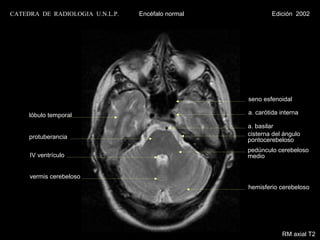

RM axial T2

CATEDRA DE RADIOLOGIA U.N.L.P.   Encéfalo normal            Edición 2002

seno maxilar

cavum

clivus

a. basilar

unión bulbo - médular

amígdala cerebelosa

hemisferio cerebeloso